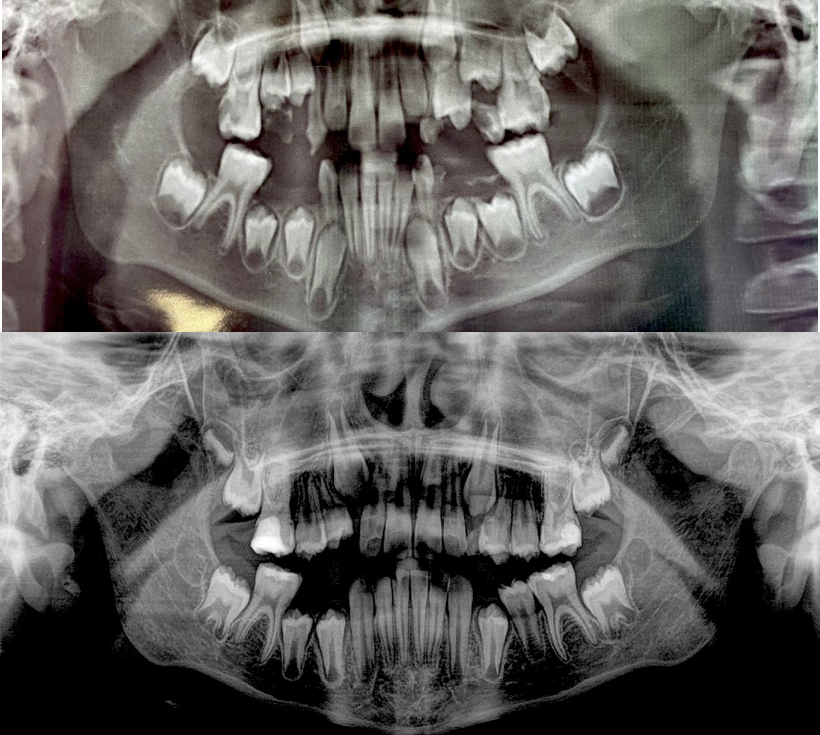

Ранній дитячий карієс , шляхи вирішення проблеми, особливості лікування

Сучасний погляд на лікування карієсу – нові стандарти , затверджені в Україні. Способи відновлення коронок тимчасових зубів.

Ендолікування тимчасових зубів, де межа між лікуванням та видаленням. Нові стандарти лікування пульпітів тимчасових зубів.